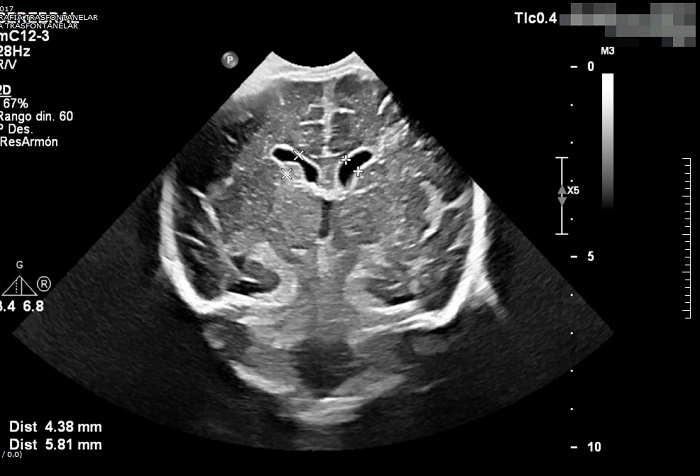

Ecografía transfontanelar. Hidrocefalia leve con prominencia e irregularidad de los plexos coroideos con posible ocupación de las astas occipitales de ventrículos laterales (de predominio derecho). Se sospecha la posibilidad diagnóstica de ventriculitis en paciente con diagnóstico de meningitis aguda.

No es posible analizar la ADA debido a interferencias por hemólisis. Debido a la alteración bioquímica en el LCR, se decide realizar ecografía transfontanelar, que muestra dilatación ventricular sugerente de ventriculitis.